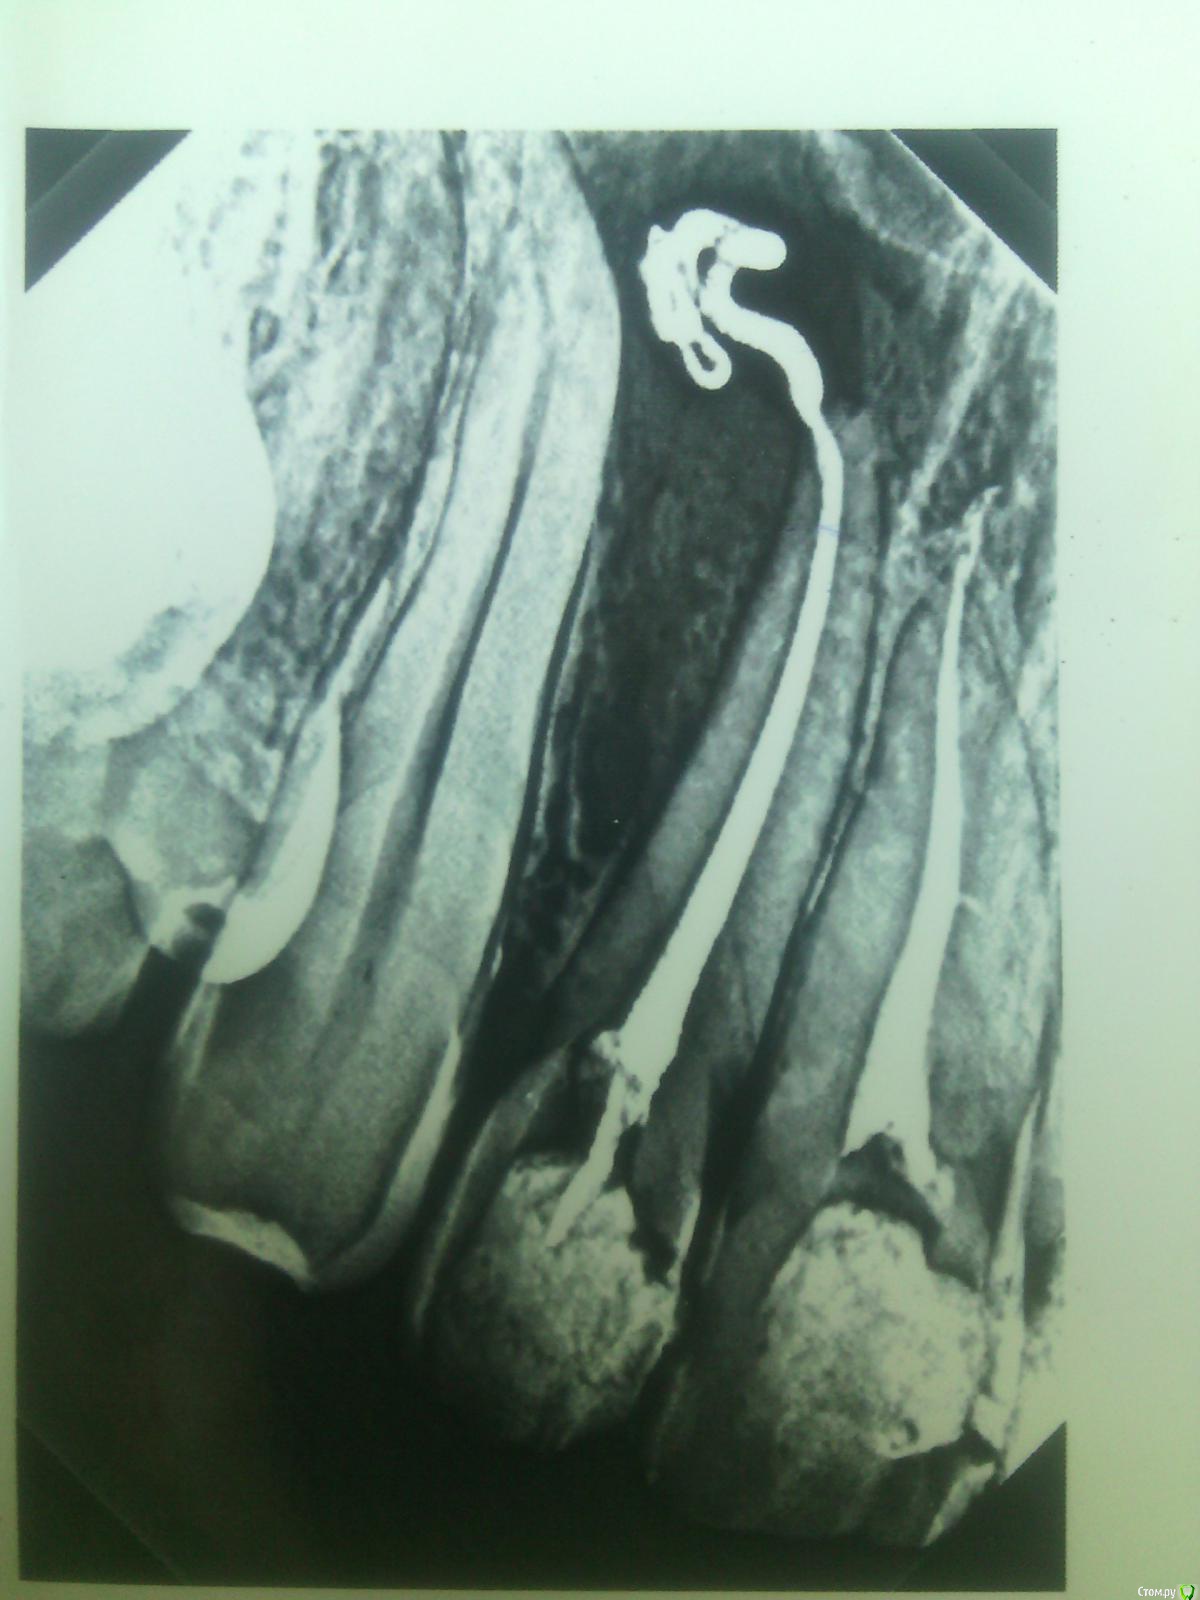

Nnoxn Опубликовано 12 июня, 2015 Автор Поделиться Опубликовано 12 июня, 2015 с депульпированием 13 не спешите , да и с 12 при адекватном лечении корневых каналов " киста " должна исчезнуть.как давно лечили 12 ? есть ли снимки до лечения? Этот снимок сделан в день, когда лечили данный канал. В канале, как я понимаю, не пломба, а лекарство, которое должно было пробыть внутри неделю. Но врач, наверное, увидев как далеко зашло лекарство сказал, что нужно делать операцию. Снимков до лечения к сожалению пока-что нет. Нахожусь в Минске, может у кого случайно есть знакомый хирург, к которому можно обратиться с консультацией? Ссылка на комментарий

Nnoxn Опубликовано 12 июня, 2015 Автор Поделиться Опубликовано 12 июня, 2015 это снимок с постоянным пломбированием каналов? 11 зуб, запломбирован постоянно, насколько я понимаю в стоматологии(а я не понимаю совсем), то гуттаперчей.1.2 - пломбировка не постоянная, на снимке лекарство, которое врач закладывал на неделю, но увидев последствия, куда оно "доплыло", сказал, что нужна операция. Ссылка на комментарий